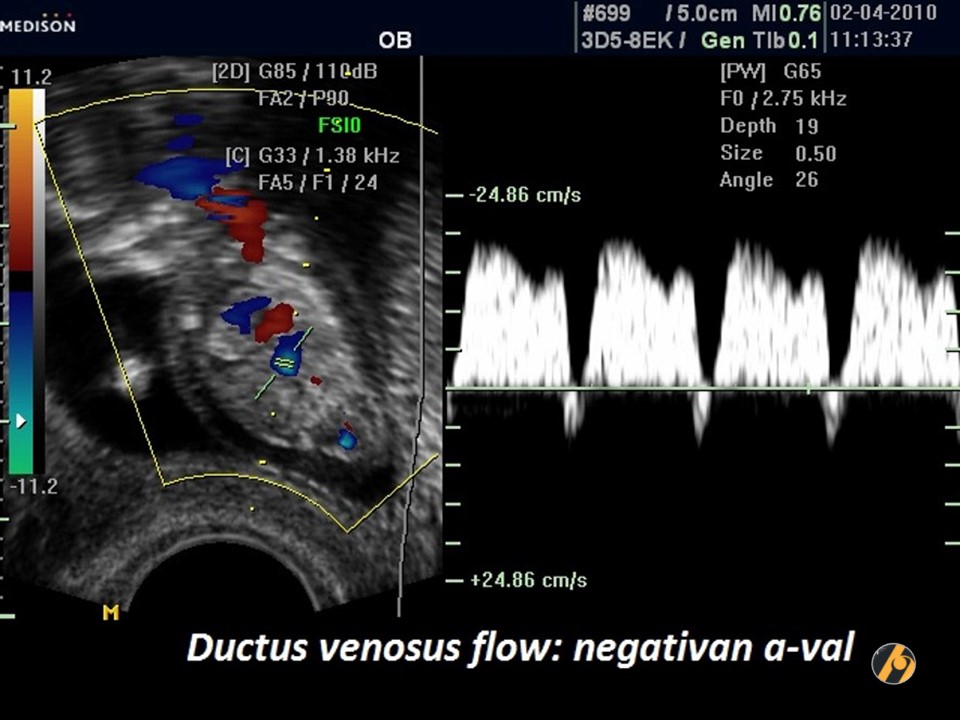

Protok kroz duktus venosus

Duktus venosus je kratka žila koja povezuje venu umbilikalis s venom kavom inferior.

Kriteriji za procjenu protoka kroz duktus venozus

Za procjenu protoka kroz duktus venozus gestacija treba biti 11 + 0 do 13 + 6 tjedana, a CRL 45-84 mm. Fetus se ne smije kretati.

Color doppler treba koristiti kako bi se prikazala vena umbilikalis, duktus venosus i fetalno srce.

Pulsni dopplerski gate treba biti mali (0,5-1,0 mm) kako bi se izbjeglo onečišćenje iz susjednih vena i trebao bi biti postavljen u žućkastom spektru protoka.

Kut insonacije bi trebao biti manji od 30 stupnjeva.

Filtar treba postaviti na nisku frekvenciju (50-70 Hz) kako bi se omogućila vizualizacija cijelog valnog oblika.

Brzina pomicanja bi trebala biti velika (2-3 cm / s) tako da se valovi prošire za bolju procjenu a-vala.

Gate: 0,5-1 mm

Low filter: 50 Hz

Sweep speed: 2cm / s

Normalan i nenormalan protok

Protok krvi u duktusu ima karakterističan oblik vala:

- Velika brzina tijekom ventrikularne sistole (S-val) i dijastole (D-val).

- Pozitivan protok tijekom atrijske kontrakcije (a-val).

Kvalitativna procjena protoka krvi kroz duktus venosus temelji se na pojavi a-vala:

- Pozitivno ili odsutno (normalno).

- Obrnuto (nenormalno).

Obrnuti val

Od 11-13 tjedana nalazi se obrnuti val u:

- euploidnih fetusa 3%

- fetusa s trisomijom 21 65%

- fetusa s trisomijom 18 55%

- fetusa s trisomijom 13 55%

Obrnuti val je češći ako je manje trajanje gestacije (gestacija je 11 nego 13 tjedana), velika debljina nuhalnog nabora, niske razine hormona PAPP-A iz majčinog seruma i ako je majka crne rase.

Obrnuti val je povezan s povećanim rizikom za kromosomske anomalije, srčane mane i fetalnu smrt. Međutim, u oko 80% slučajeva s reverznim valnim valom ishod trudnoće je normalan.